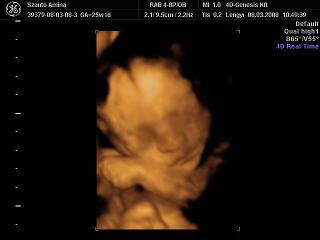

26 hetesen2007.12.13 20:04